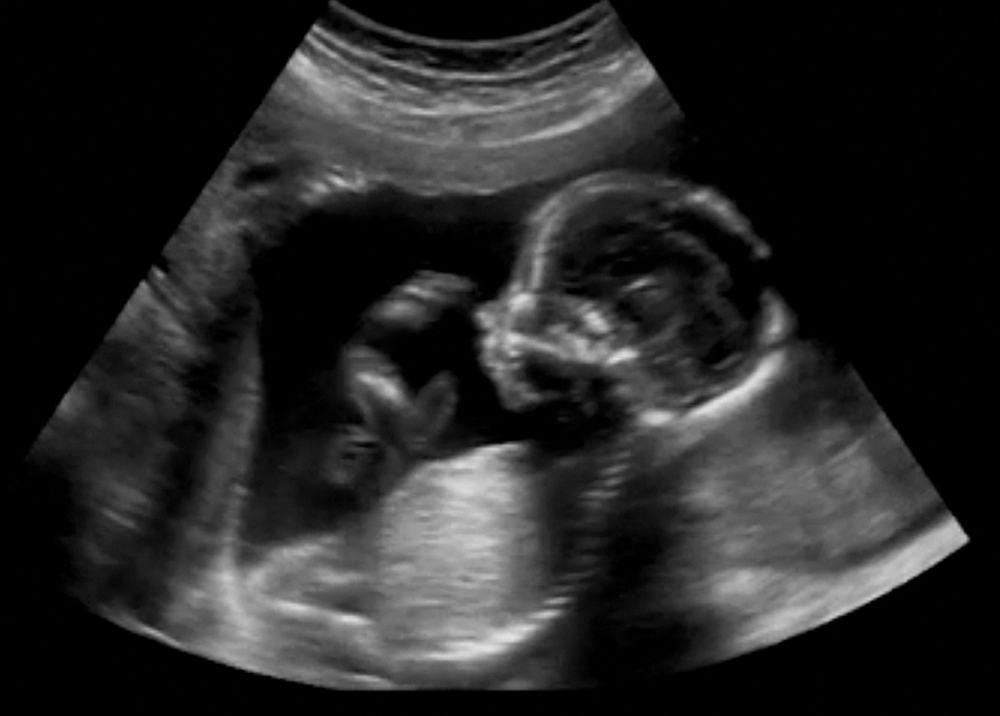

Peristiwa bayi mati sebelum usia kandungan mencapai 20 minggu biasa kita kenal dengan sebutan keguguran. Sedangkan kondisi bayi yang mati di usia kehamilan lebih dari 20 minggu dinamakan dengan bayi lahir mati atau stillbirth. Banyak orang menganggap bahwa keguguran adalah semua kematian bayi sebelum ia lahir ke dunia, padahal kondisi tersebut bisa berbeda tergantung dari usia kehamilan ibu saat bayi dikatakan meninggal.

Bayi lahir mati dapat disebabkan oleh berbagai hal, seperti kondisi ibu, janin, dan juga plasenta. Kecukupan gizi ibu selama hamil juga dapat memengaruhi risiko bayi mengalami lahir mati. Berikut ulasan lengkap berbagai penyebab dan faktor risiko terjadinya stillbirth.

Satu dari 200 kehamilan dapat mengalami kematian sebelum bayi lahir pada usia kandungan lebih dari 20 minggu. Tidak jauh berbeda dengan penyebab dari keguguran, bayi lahir mati juga bisa disebabkan oleh kondisi ibu maupun janin. Berikut ini beberapa penyebabnya.